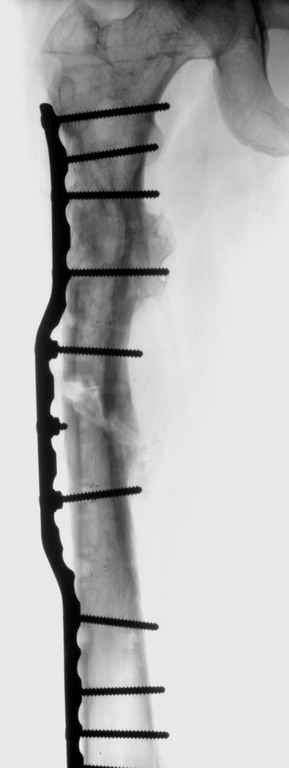

Можно применить гвоздь с множественными косыми остеотомиями, но я посчитал, при применении 4.5 мм длинной пластины или L-образную пластину с короткой ножкой в шейку, шанс на удержание отломков более вероятная, чем гвоздем.

Двойную остеотомию при лечении можно делать так: латеральным субвастус доступом (с приподниманием вастус латералис) обнажается латеральная поверхность бедра, заранее сделанным преоперационнным планом определяется место остеотомии, периостиум обнажается только по этому

плану, т.е. по линии остеотомии. Перед остеотомией накладывается дистракционный аппарат, делается остеотомия и медленная дистракция, накладывается по длине пластина, дистракция и компрессия по

необходимости, фиксируются проксимальный и дистальный концы пластины 4.5 мм шурупами, косо для стабильности, затем работа с медиальным

фрагментом.

Необходимо создание медиальной компрессии, которая создастся с помощью коротких шурупов против латерального кортекса. Чтобы эти шурупы не выпали из дырок на пластине, надо применить резьбовую шайбу Schulle nut, который имеет резьбу точно подходящую к резьбе шурупа, и ставится с внутренной стороны пластины, те конструкцию locking plate.